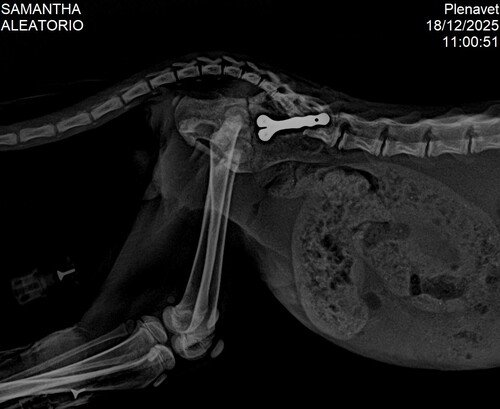

A cirurgia foi um sucesso! Hoje, o Madruguinha está estável, ativo, comendo, interagindo e, aos poucos, retomando a vida que quase lhe foi tirada. Ele venceu a parte mais dura da história, mas ainda precisa de apoio.